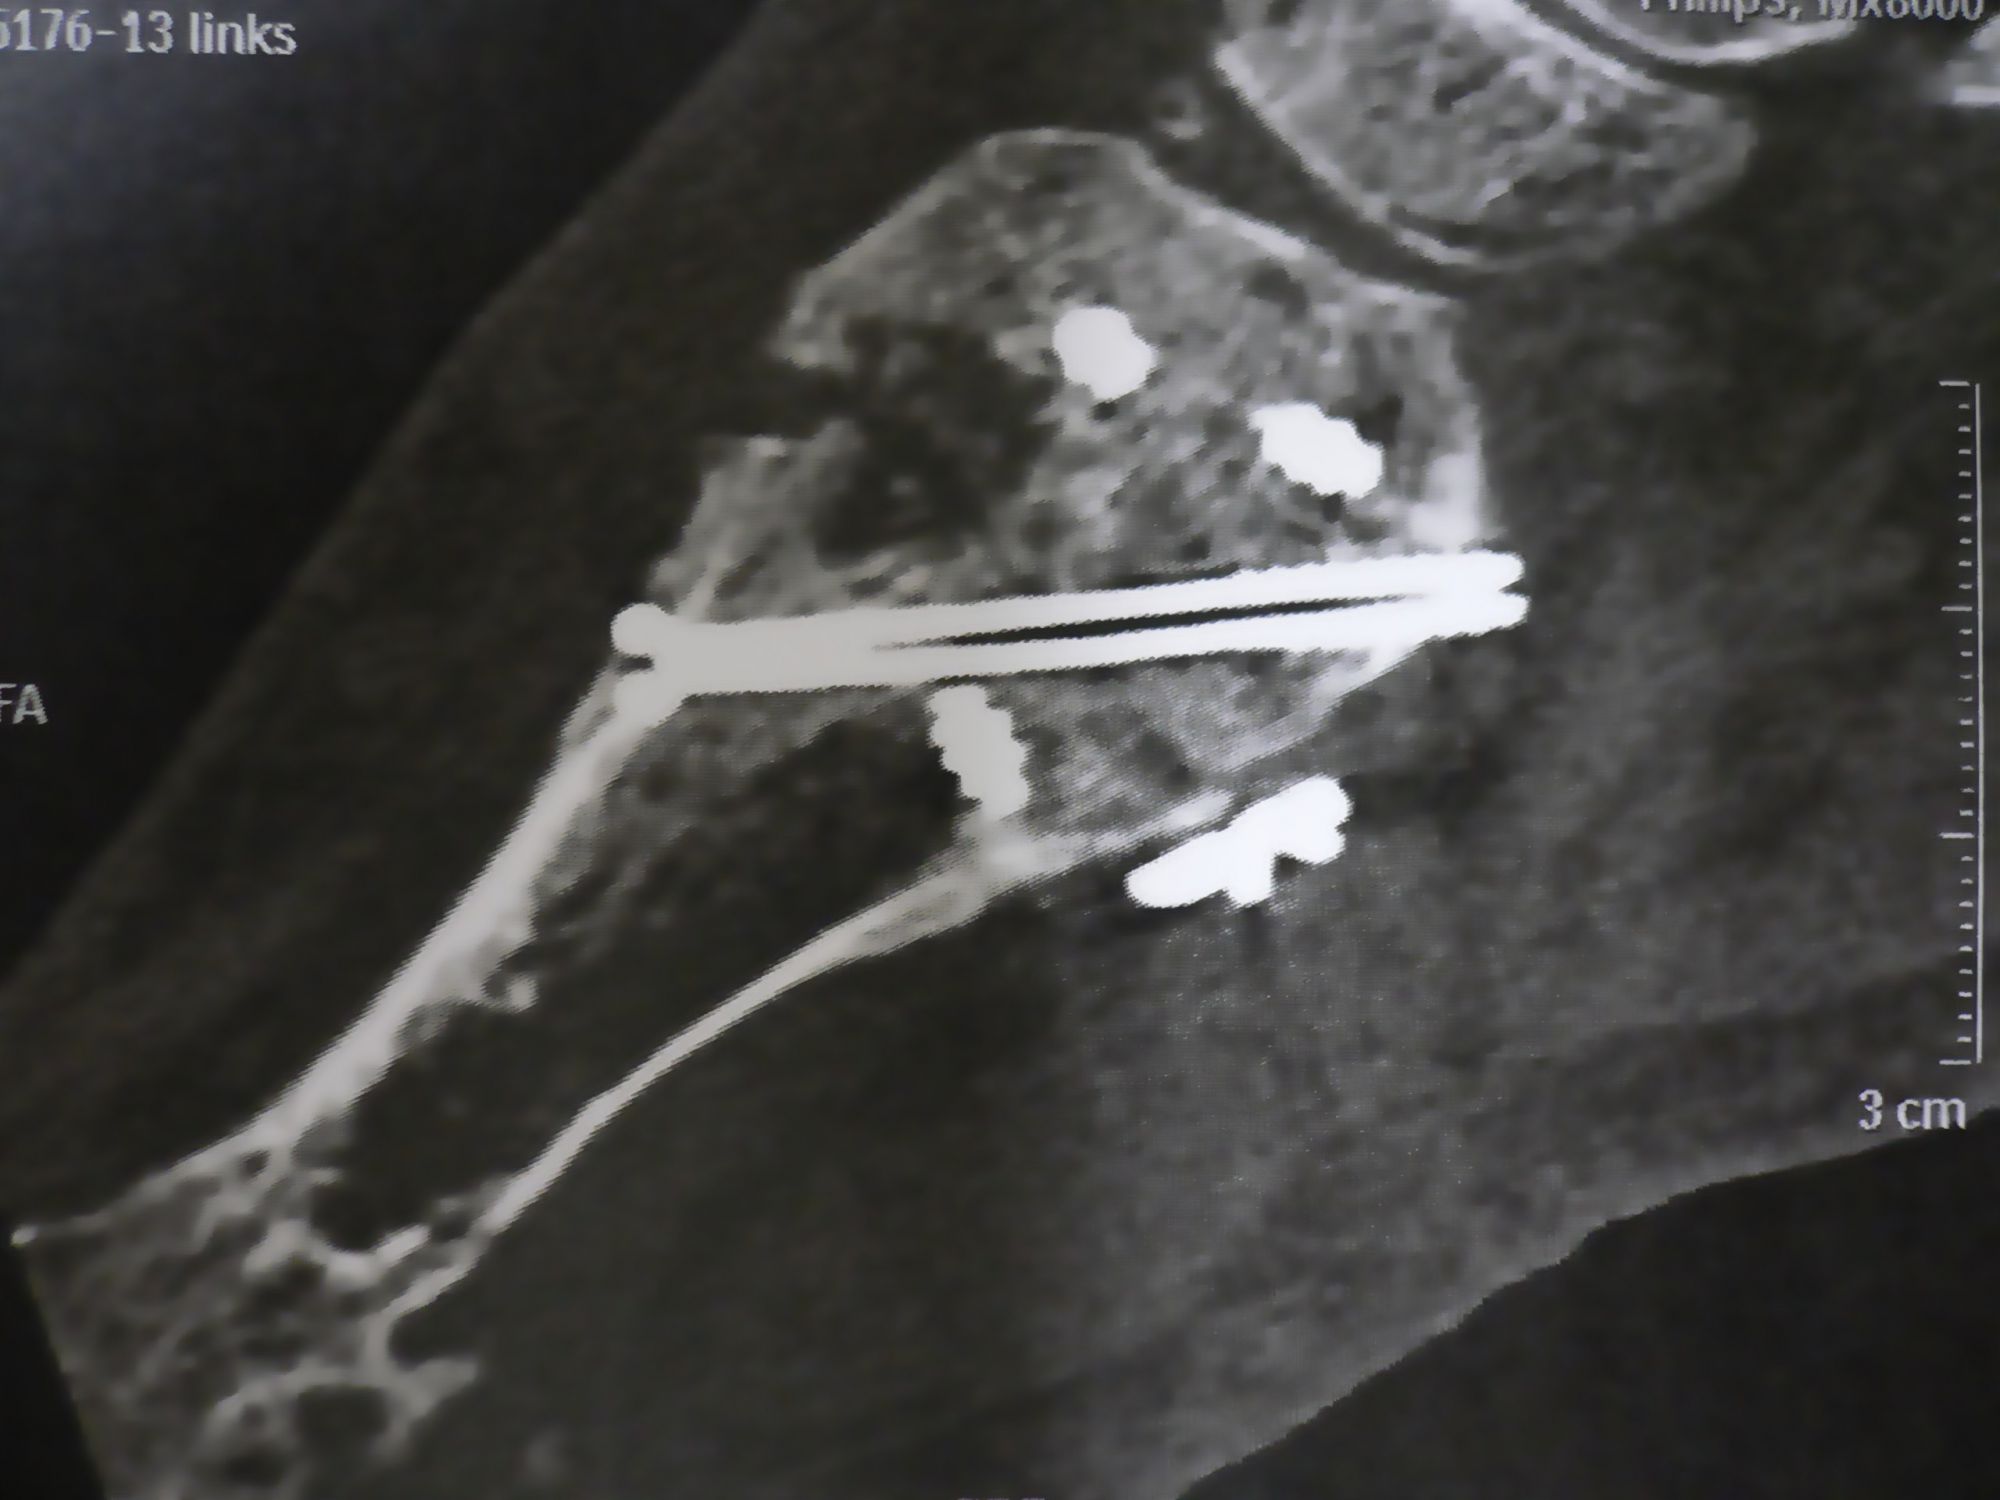

Pseudarthrose: Kommt es innerhalb von 6 Monaten zu keiner knöchernen Durchbauung, ist eine operative Revision indiziert. Ist anhand der normalen Röntgenaufnahmen in 4 Ebenen die Arthrodese nicht sicher zu beurteilen, kann mit Hilfe eines Computertomogramms die Überbauung sicher eingeschätzt werden (Abb. 12). Nach Ausräumung der Pseudarthrose und Spongiosaanlage vom Beckenkamm erfolgt die Reosteosynthese mit einer winkelstabilen Platte. Die Nachbehandlung nach Pseudarthrose umfasst eine 6-wöchige Phase der Entlastung im Castverband. Anschließend Belastungsaufbau nach Röntgenkontrolle. Insgesamt ist die Pseudarthrose eine seltene Komplikation der Arthrodese des TMT 1-Gelenks mit plantarer Osteosynthese.

Zum Lesen der Bildbeschreibung und zur Vollansicht bitte das Bild anklicken.

Abbildung 12